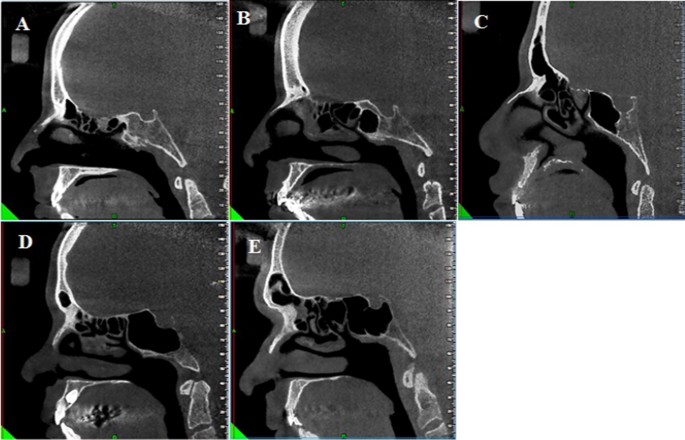

A Presellar Type Of Sphenoid Sinus B Postsellar Sphenoid Sinus In Download Scientific Diagram

Sphenoid Sinus And Related Neurovascular Structures Anatomical Relations And Variations On Radiology A Retrospective Study Springerlink

Cone Beam Computed Tomography Analysis Of Sphenoid Sinus Pneumatization And Relationship With Neurovascular Structures Springerlink

The Impact Of Sphenoid Sinus Pneumatization Type On The Protrusion And Dehiscence Of The Adjacent Neurovascular Structures A Prospective Mdct Imaging Study Academic Radiology